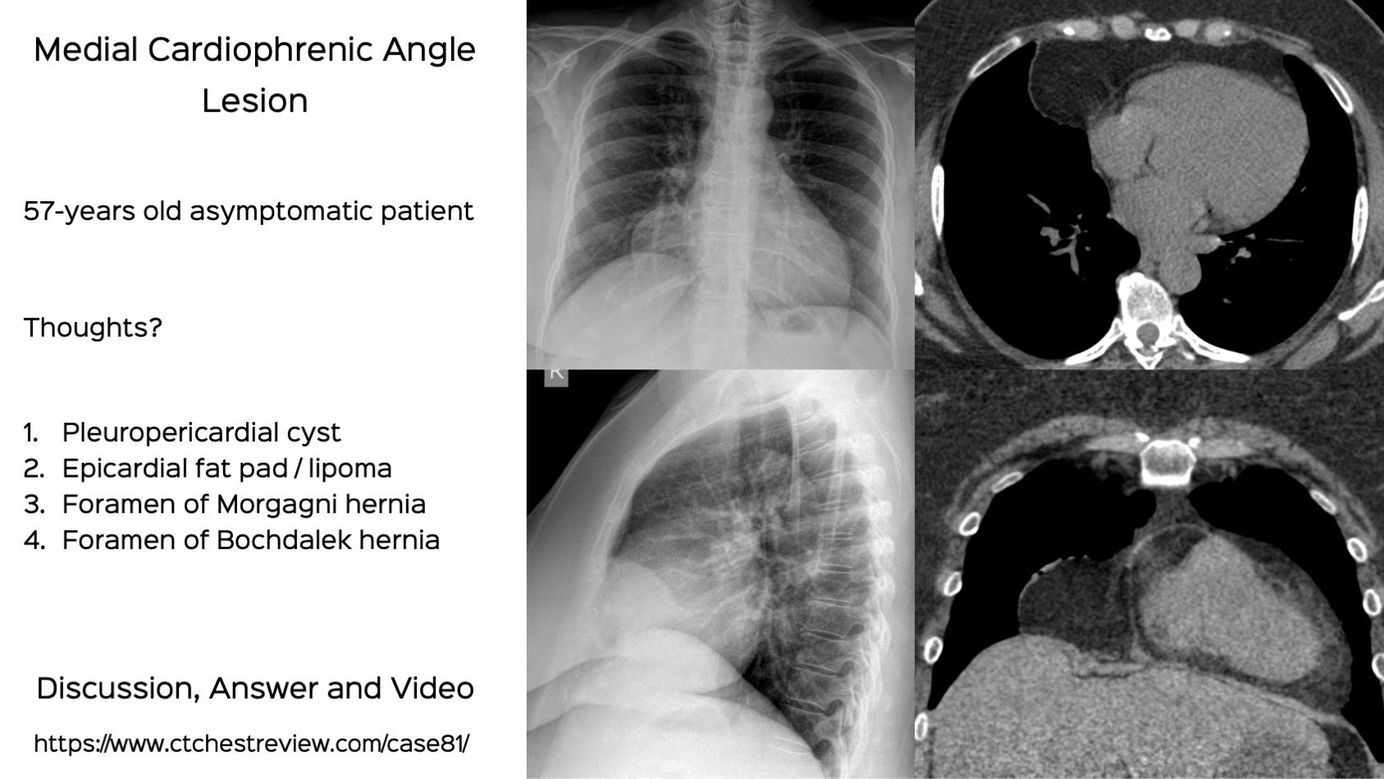

Case 81: Medial Cardiophrenic Angle Lesion Members Public

The differential of a medial cardiophrenic angle lesion is limited

Mediastinum